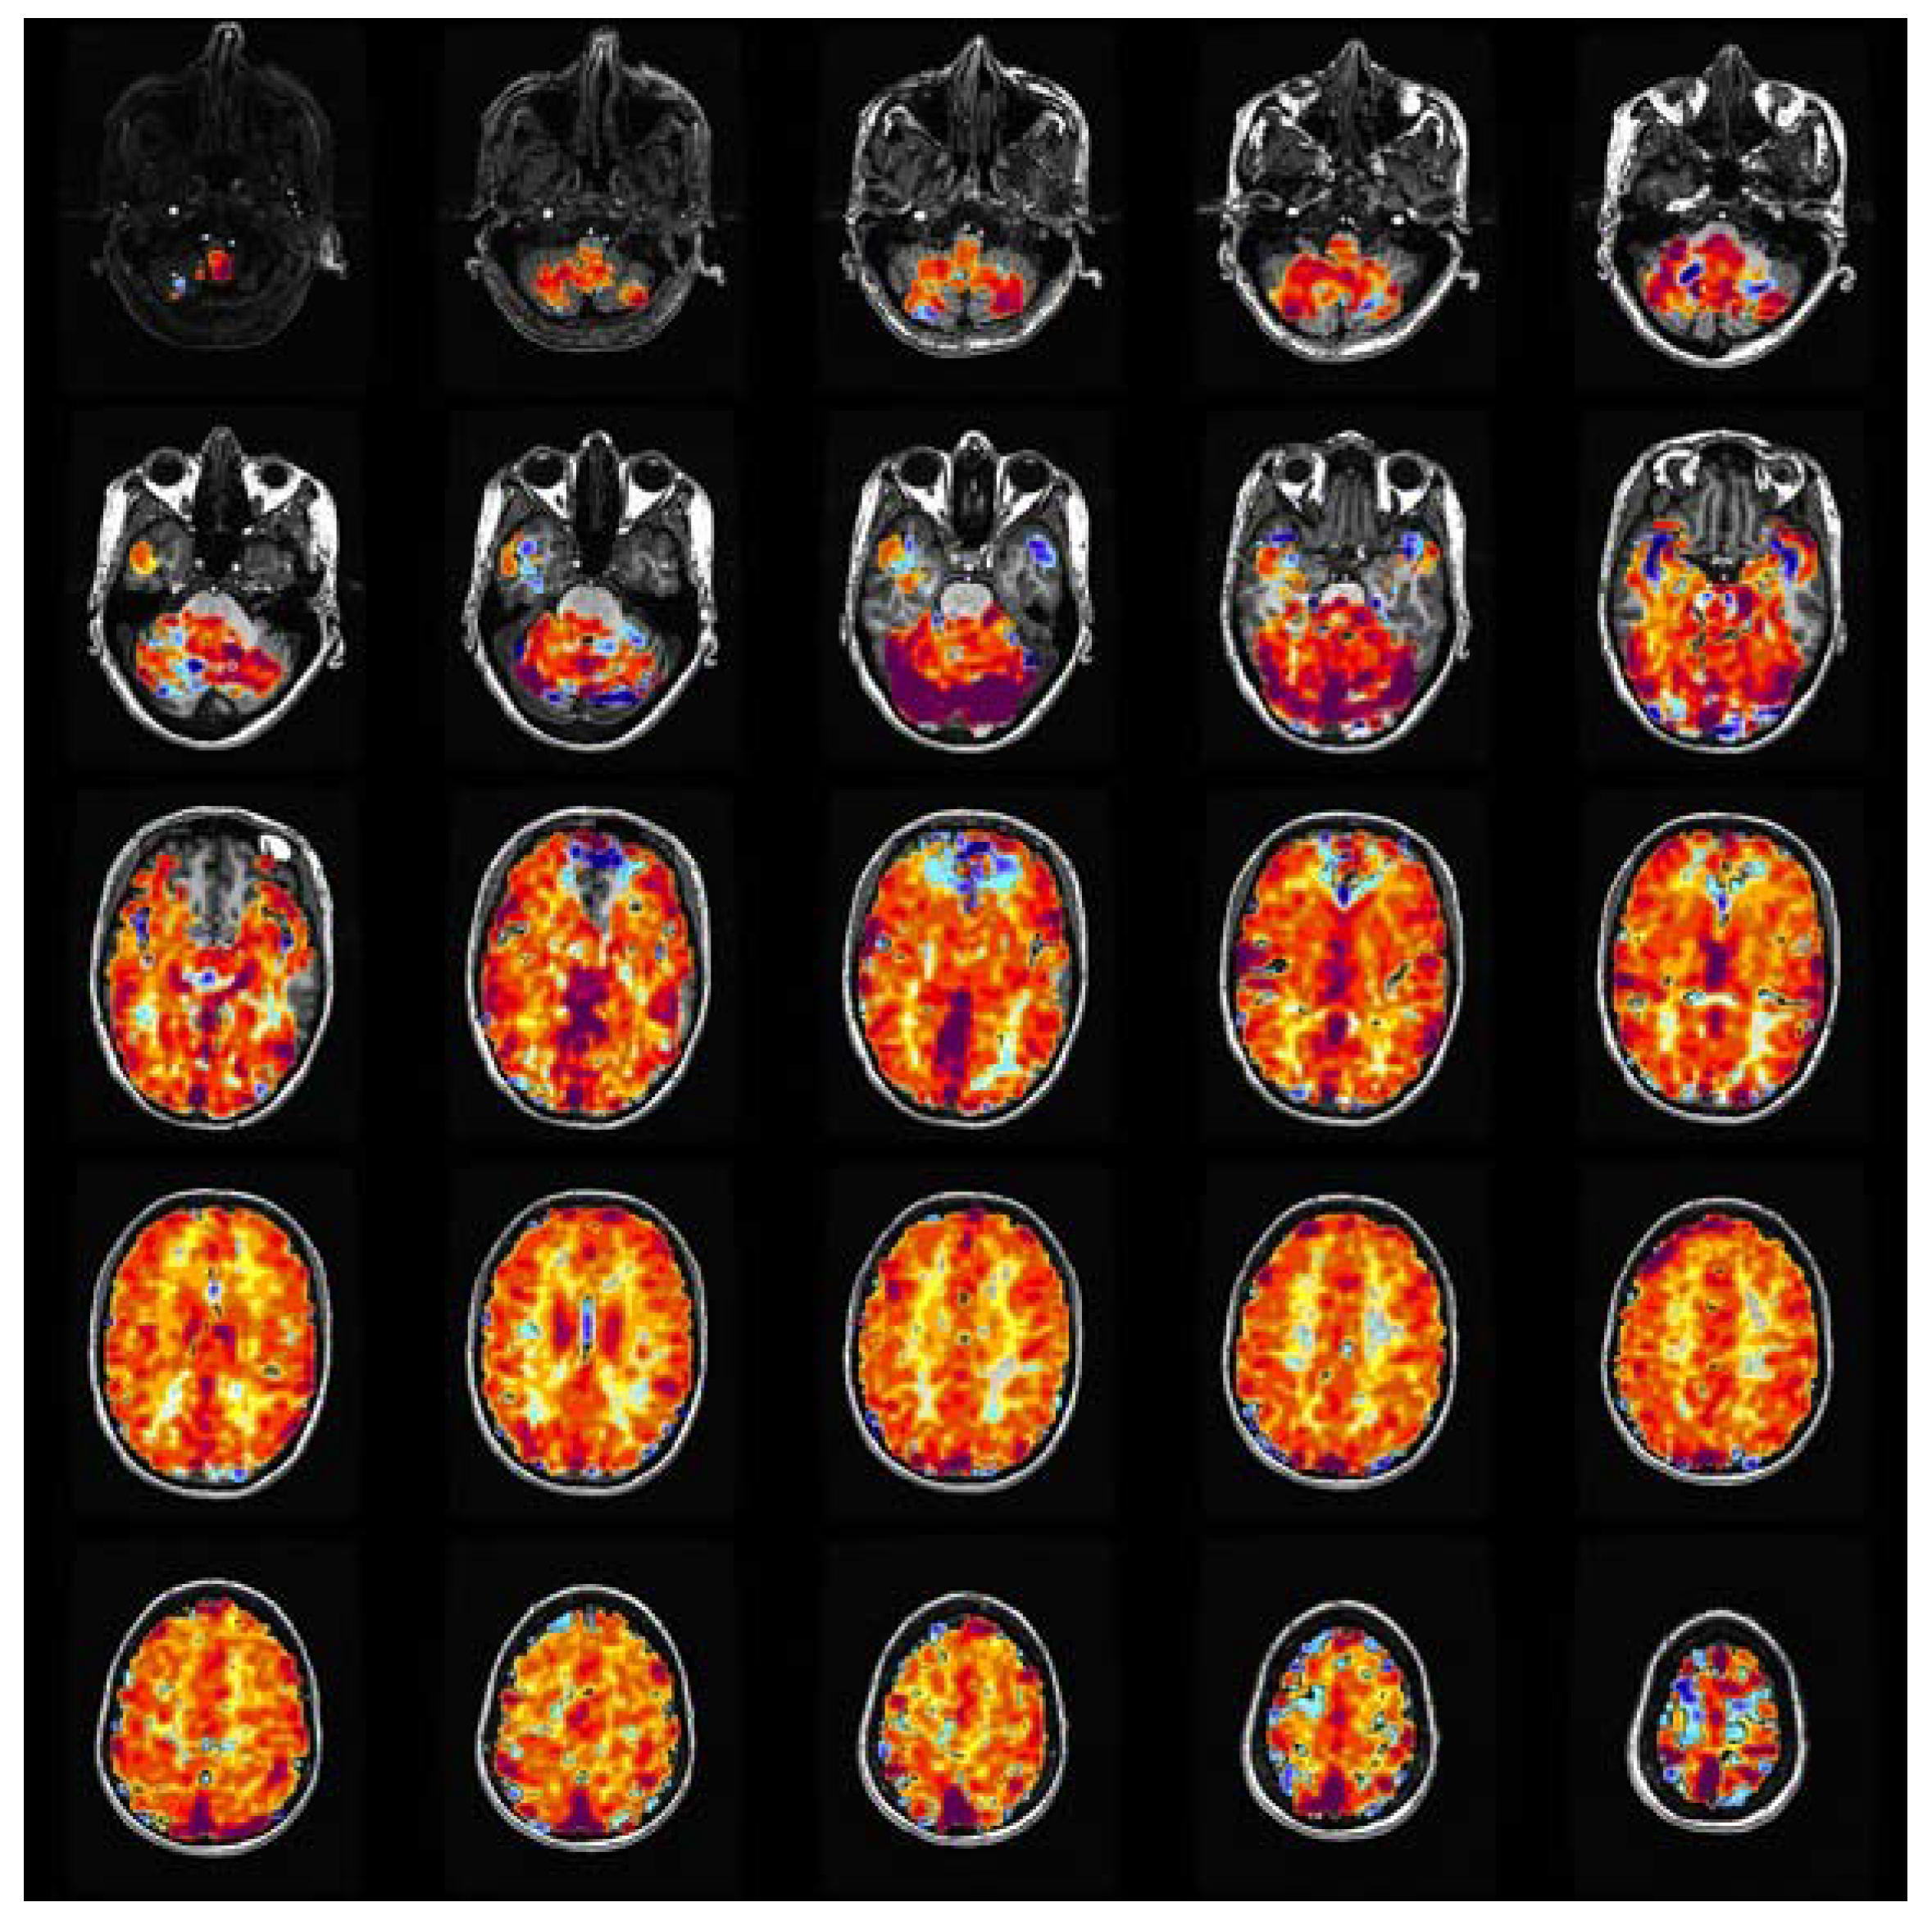

1.1. CVR: Clinical Workflow

3.1. Data Analysis and Pre-Processing